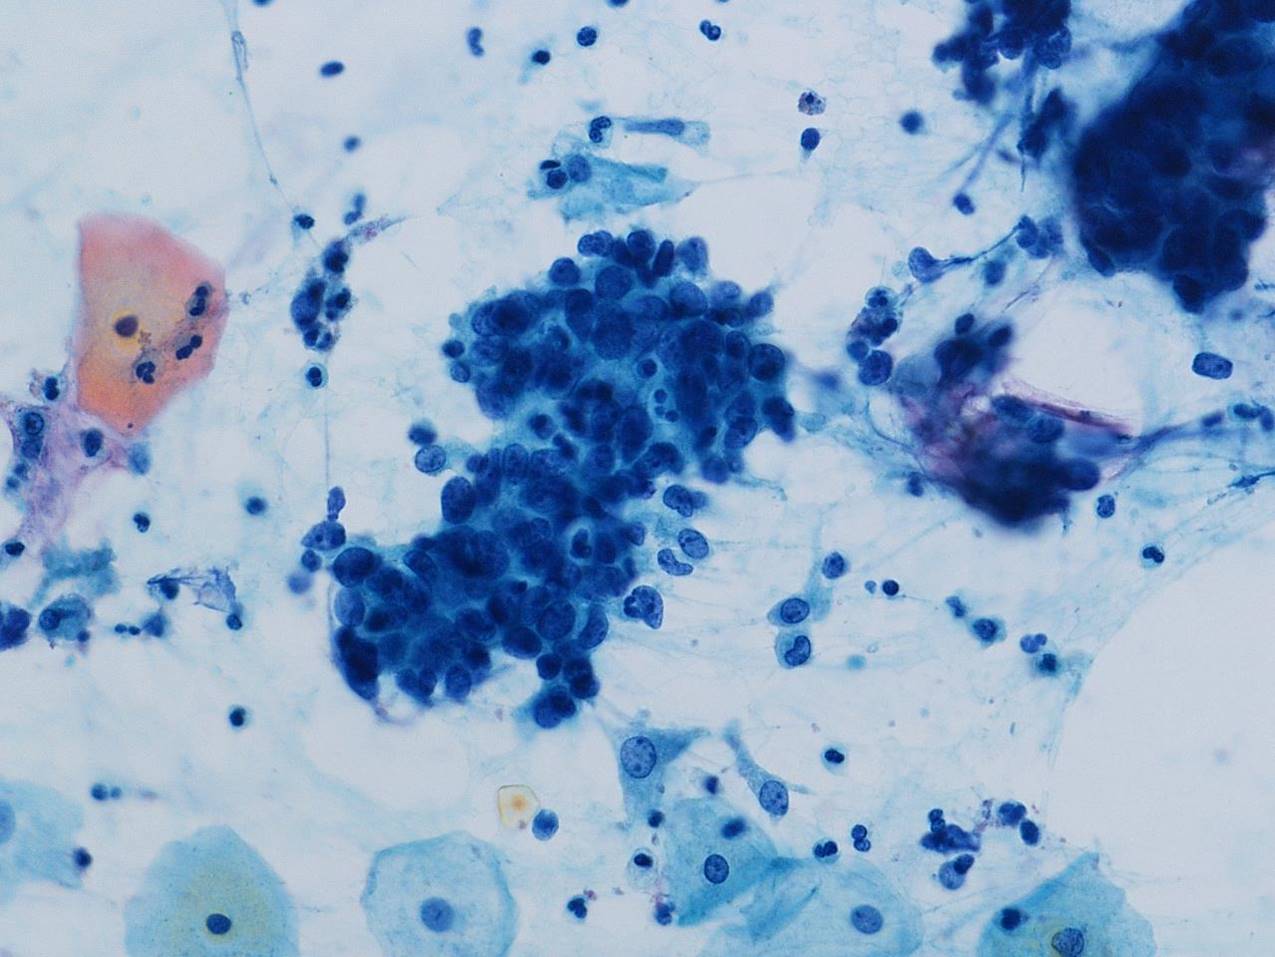

細胞診所見

背景に壊死物質は認められなかった。その中に偏在性核で核クロマチン増量を示す腺系異型細胞の不整形集塊を認めた。柵状配列や腺管構造もみられ上皮内腺癌を疑う細胞と考えた。またN/C比が高く細顆粒状の核クロマチンを有する傍基底型核異常を疑う細胞もみられた